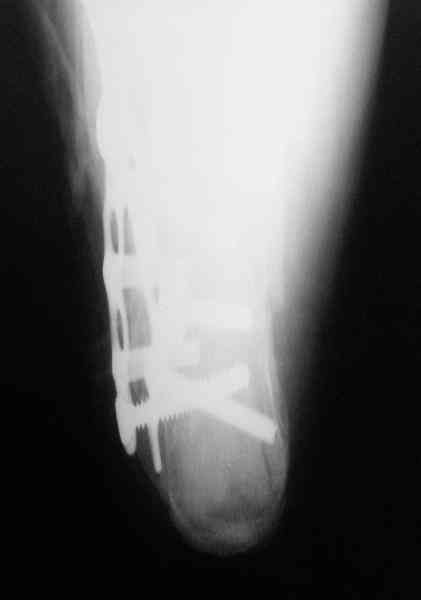

Re: Перелом пяточной кости

Пяточной пластиной